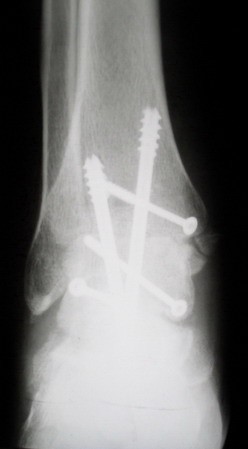

В итоге: мы планируем выполнить пациенту большеберцово-пяточный артродез в аппарате Илизарова с одновременной остеотомией берцовых костей и их последующим удлинением. Возможно, мы дополним фиксацию артродезируемых костей винтами.

При применении шурупов для фиксации, рекомендуется применение 6.5 или 7мм каннулированных шурупов с шайбой, через пятку направленному к переднему кортексу (придасть стабильность) большеберцовой и если имеется возможность провести второй паралельно или под углом, причем на разных уровнях кортикального слоя иначе спереди большеберцовой

образуется стрессовая зона. Для контроля ненужного эквинуса при затягивании шурупов рекомендуется

задний шуруп затягивать первым и дополнительный вертикальный шуруп при сомнении на стабильность.

Остеотомия дистального конца малоберцовой с укорочением и с удалением внутренней половины уменьшает диаметр внизу и создает натуральный

контур голени.